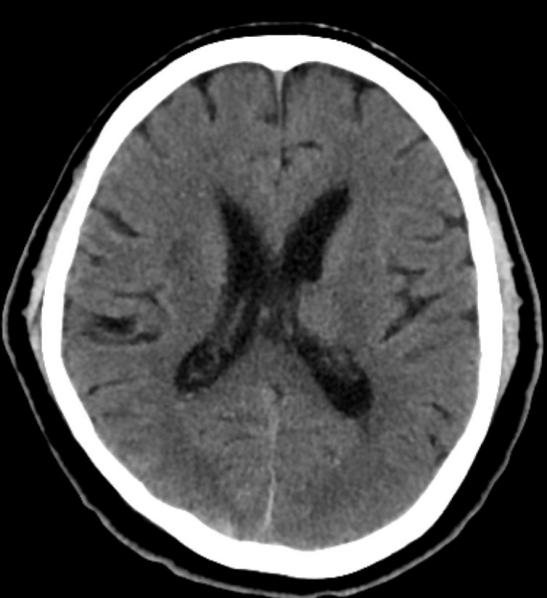

术后患者转入ICU,接受机械通气、镇静镇痛、防治脑血管痉挛、脱水降颅压等治疗。复查头颅CT见颅内出血逐渐减少,无脑梗死及脑积水。术后一周拔除脑室引流管,行气管切开术。患者病情逐渐好转,术后3周脱离呼吸机,转至当地康复医院继续治疗。出院时患者能自动睁眼,左侧肢体可活动。

▲脑室引流前